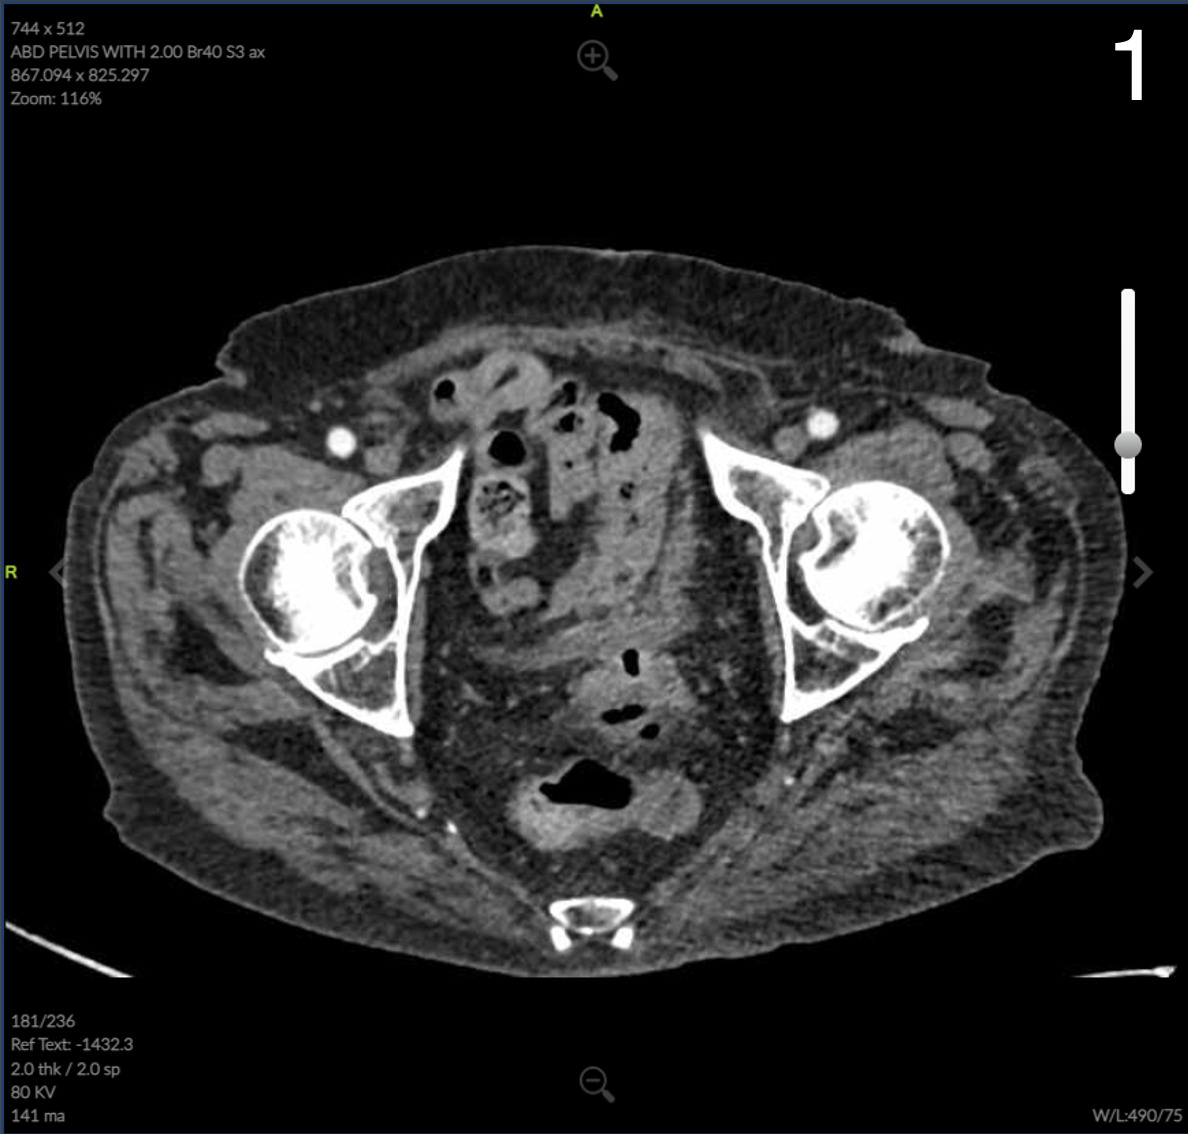

Computed Tomography (CT) of the abdomen and pelvis showed colonic wall thickening particularly in the pelvis close to the vaginal vault. A colonoscopy revealed a severe kink that could not be crossed in the sigmoid colon and extensive diverticular disease.

Pathology of the colonic portion of colovaginal fistula revealed severe acute on chronic diverticulitis with stricture, perforation, and fibrinous serositis with adhesions consistent with clinical history of colovaginal fistula negative for dysplasia or malignancy. The anastomotic donuts were benign and viable colonic mucosa was negative for dysplasia or malignancy. Review of microbiology of the vaginal canal revealed detection of only normal vaginal flora that was negative for G. vaginalis, T. vaginalis, N. gonorrhoeae, C. trachomatis, and C. albincans.